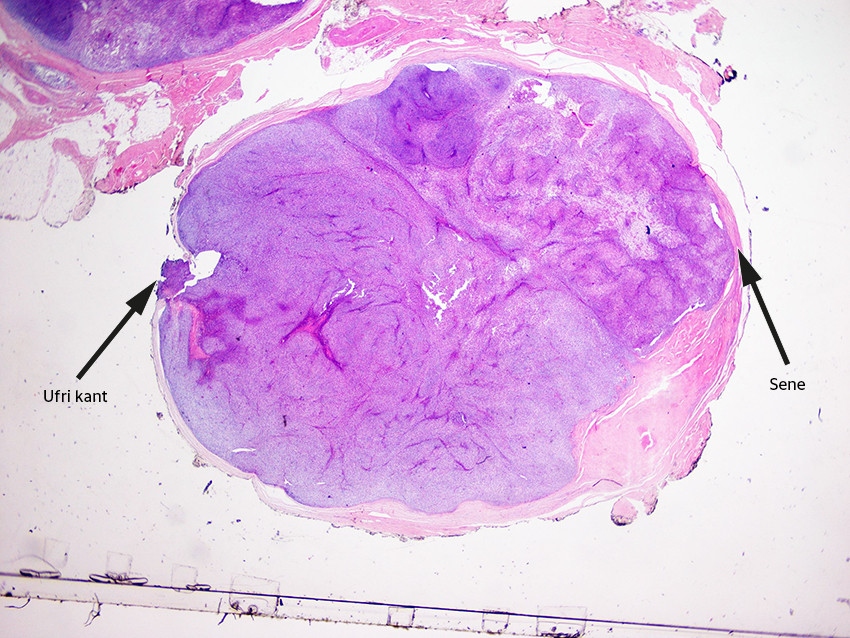

Få dager senere kom foreløpig svar fra patologen om at morfologisk passet bildet med en malign tumor, der både synovialt sarkom og malign perifer nerveskjedetumor er differensialdiagnostiske muligheter. Det var tumorvev i reseksjonskanten i et lite område. Immunfenotypiske undersøkelser bekreftet at man hadde å gjøre med synovialt sarkom, fransk malignitetsgrad 3 (figur 4 og 5).

Overraskelsen vi fikk, har fått betegnelsen whoops-kirurgi (etter engelsk whoops procedure), som beskriver en utilsiktet marginal eksisjon av en tumor som viser seg å være et sarkom. Bekymringen er at dette kan spre tumorceller og vanskeliggjøre en senere og mer radikal eksisjon. Fenomenet ble først problematisert i 1985, og er ganske vanlig, spesielt ved mindre tumorer uten typiske maligne karakteristika (5, 6).

Behandlingen er i de fleste tilfeller ekstremitetsbevarende vid eksisjon fulgt av strålebehandling med eller uten kjemoterapi. Vid eksisjon av tumorer i hånden er imidlertid ofte problematisk på grunn av nærhet til nerver og sener med avgjørende betydning for håndfunksjonen. Ved lokalisasjon nær viktige nerver kan marginal eksisjon være aktuelt, selv om mer radikal eksisjon er vesentlig for å redusere sjansen for lokalt residiv (6, 9). Synovialt sarkom, som var diagnosen i vårt tilfelle, er kjent for å være vanskelig å diagnostisere klinisk og radiologisk, og har høy residivrate. Residiv selv etter mer enn ti år er dokumentert (14). Femårsoverlevelse ved bløtvevssarkom i hånden er estimert til 80–90 % (9, 15).